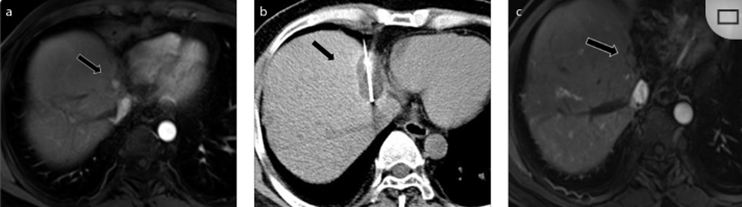

79 岁男性,肝转移(结直肠癌)肿瘤的完全消融病例

( a ) 轴向 MRI 和 ( b ) 轴向 CT 显示肝S8段有一个16mm的病灶,邻近肝缘。( c )冷冻消融期间CT显示放置了2个冷冻探针,低密度冰球包围病灶。(d)术后1个月随访 CT显示冰球对应的坏死区域,未见复发。(f)与基线影像(g)相比,12个月后的FDG-PET/CT显示未见FDG摄取。

(a)轴向CT显示病变位置毗邻心脏和上腔静脉(黑色箭头)。1个月后的轴向(e)和冠状位(f)增强CT扫描显示低密度区域,由于肉芽组织反应引起的边缘增强。